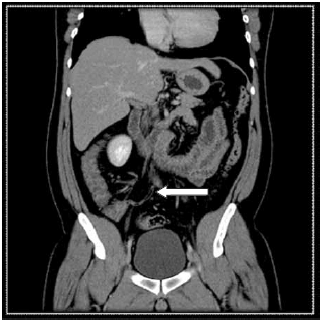

Observe a imagem tomográfica.

Pode-se afirmar que o plano de corte e a estrutura sinalizada são, correta e respectivamente,